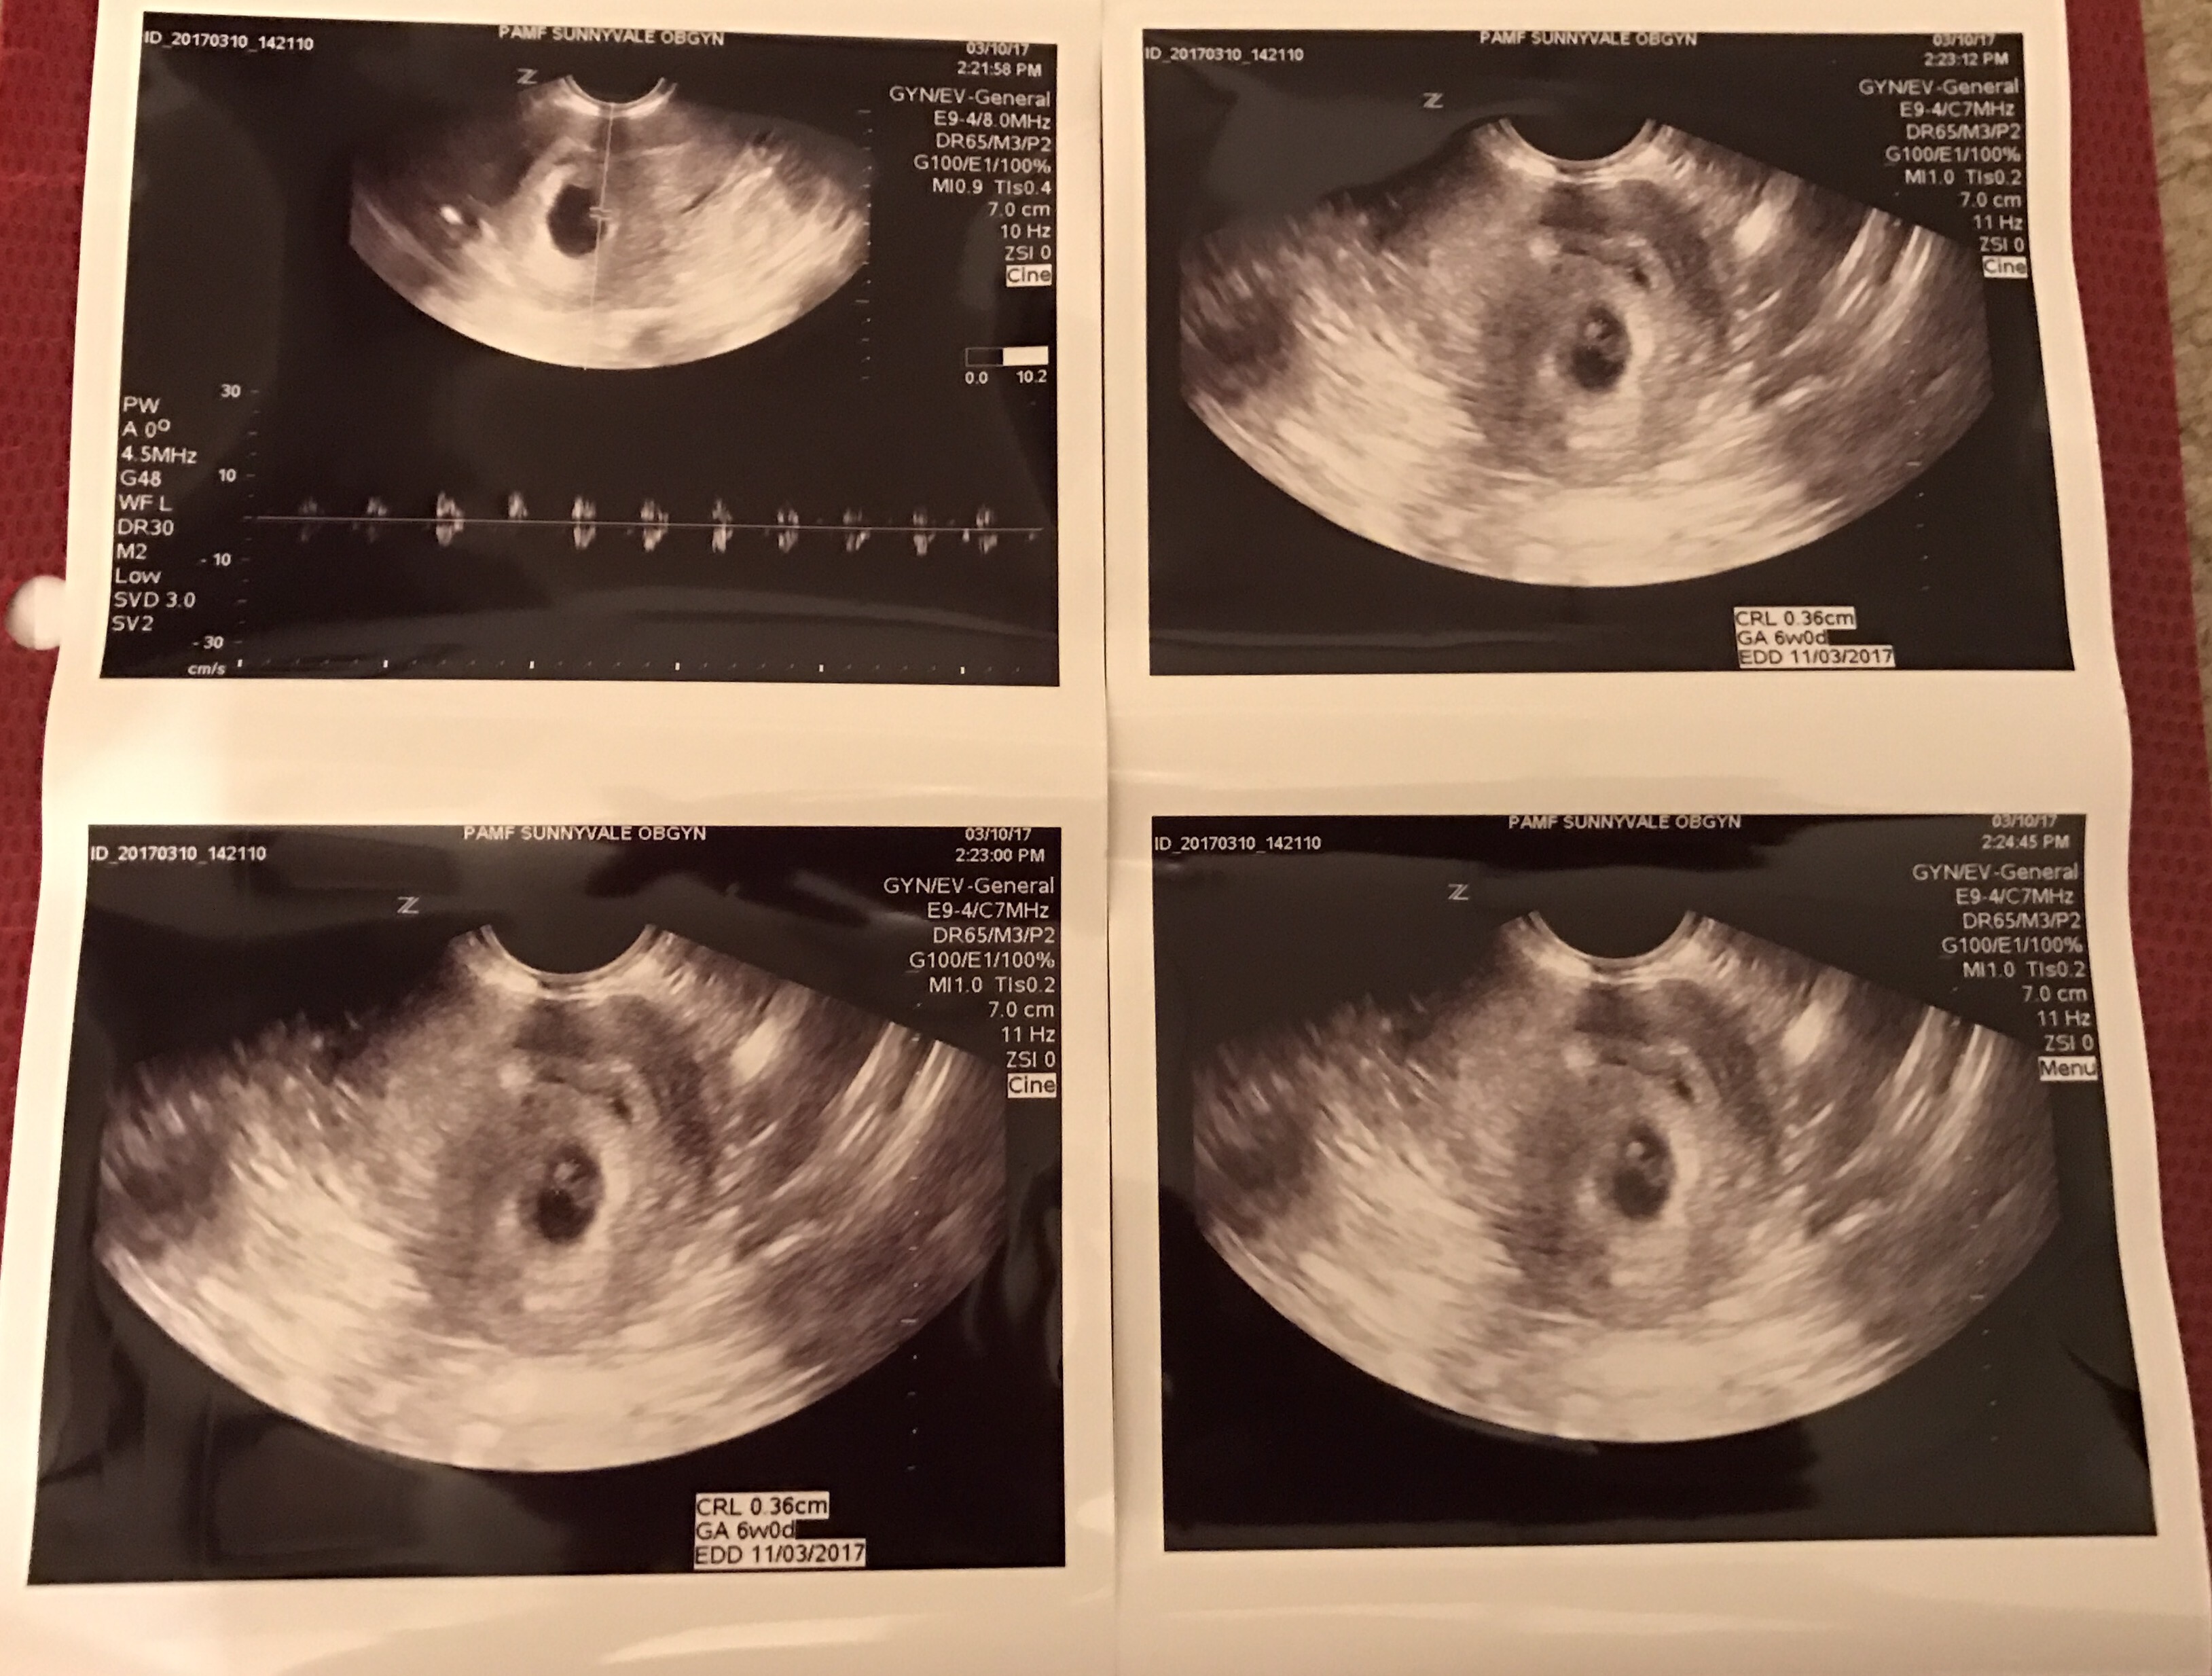

To the surprise of my husband and myself I received a notice on Saturday from my insurer that they would not be paying a bill for $427. It took both my husband and I calling them to get clarification, at first I was told it was for radiology which makes no sense as I haven’t had an X-ray in years though I have had two sonograms. The bill was for this, the first uktrasound I received which estimated my then embryo at 6 weeks.

I spent over an hour taking with the representative and Matt spoke to them hours later. Despite a screen shot of the benefits of our policy including that has one word next to Prenatal Program: covered. The representative Matt spoke to said that it was confusing and that the ultrasound was for maternity not prenatal. Aren’t they the same thing, apparently the rep didn’t explain them as being all that different, so we’re stumped. We are confused at this point and we are going to appeal.

I’ve had two ultrasounds and will probably have another at my next appointment next Wednesday when I’ll be 10 weeks and 2 days. In addition to helping document our baby’s growth the tests help determine the health of our baby. I will do whatever I can to help our baby grow healthy and strong and as a proud resister already, if the insurance company wants a fight on benefits that clearly appear to be covered by them, they’ll get one!